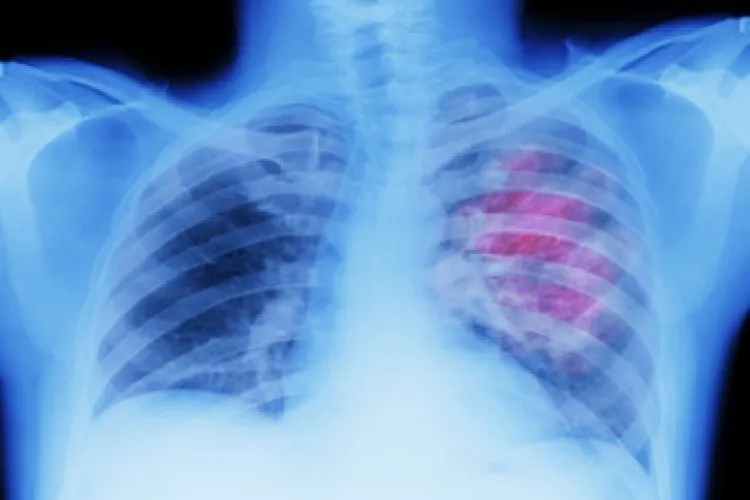

على الرغم من أن سرطان الرئة لا يظهر عادة أعراضا في المراحل المبكرة، فقد تظهر العلامات التحذيرية مع تقدم الحالة.

وعندما تفكر في سرطان الرئة، قد تتبادر إلى ذهنك أعراض مثل السعال أو ضيق التنفس. وبصرف النظر عن رئتيك وصدرك، هناك منطقة أخرى يمكن أن تشير إلى الحالة - الأصابع. وشارك مركز أبحاث السرطان في المملكة المتحدة أن إحدى العلامات التي يمكن أن تكون أحد أعراض سرطان الرئة هي تعجر الأصابع.

ويمكن رصد هذه الأعراض الخاصة بين المرضى الذين يعانون من مشاكل في الرئة والقلب، بما في ذلك سرطان الرئة. ومن اللون الخفيف إلى المنحنى، هناك عدد قليل من العلامات الدالة على تعجر الأصابع.